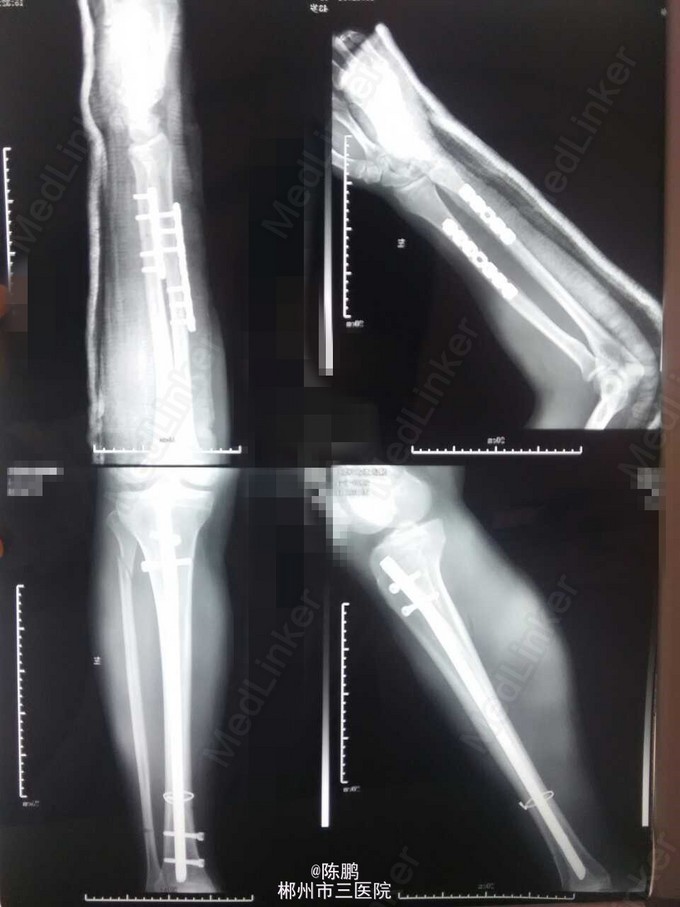

专科体查:左前臂明显肿胀,局部皮肤青紫,压痛,纵向叩击痛,可扪及明显骨擦感及闻及骨擦音,左前臂活动受限,左桡动脉搏动可,左小腿少肿胀,局部皮肤青紫,压痛,纵向叩击痛,中下1/3处可扪及明显骨擦感及闻及骨擦音,左小腿活动不能,左足背动脉搏动可,肢端血运感觉可,余肢体及脊柱未见异常。 辅查:x线示:左尺桡骨,左胫骨下段,左腓骨上段骨折

诊断:1.左尺桡骨骨折 2.左胫骨下段腓骨上段骨折 3.头部外伤:1)脑震荡 2)头皮挫裂伤 3)颅内血肿脑挫裂伤待查 行左胫骨下段骨折切开复位带锁钉内固定及左尺桡骨下段骨折切开复位,钢板内固定术